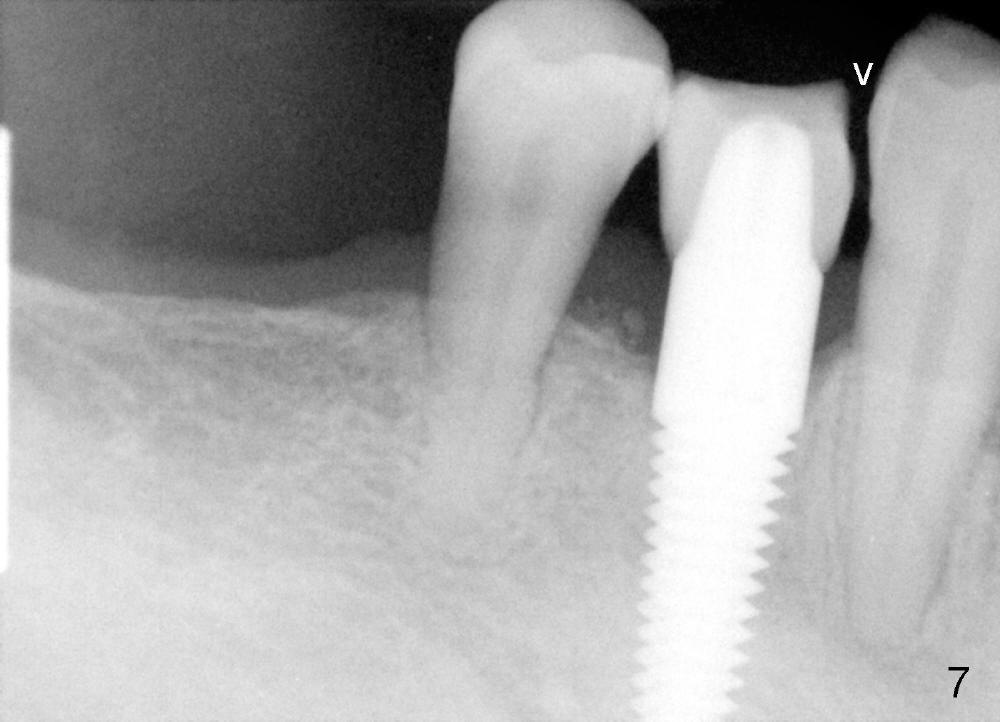

A 66-year-old man has poor dentition (Fig.1). Several teeth (x) including #28 need extraction and implants. The tooth #28 is extracted (Fig.2), followed by immediate implant (5x17 mm, Fig.3 I). There is more buccal gingival recession over the implant (Fig.4), which is less prominent 1.5 months postop (Fig.5). The definitive restoration is delivered less than 2 months postop (Fig.6), because of travel abroad. The patient agrees not to chew with the Emax crown. Five months later, he returns with chipped porcelain (Fig.7 arrowhead). It appears that immediate implant can survive early and over loading. More implants are necessary to share the masticatory loading. Since there is malocclusion, where to place implants appears to be critical (Model 3 30 4 5 6 7). There is no bone loss 4.5 years (Fig.8) or 5 years 8 months (Fig.9) post cementation.